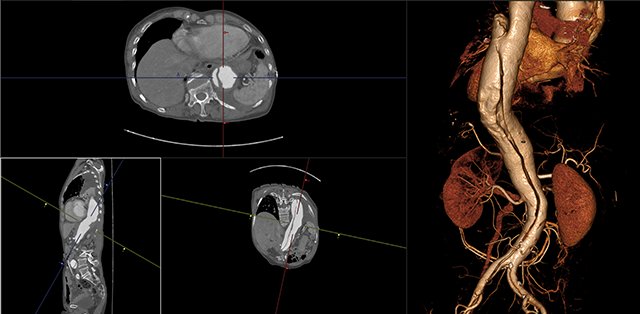

ANYTHINK 经导管主动脉瓣膜置换术分析系统